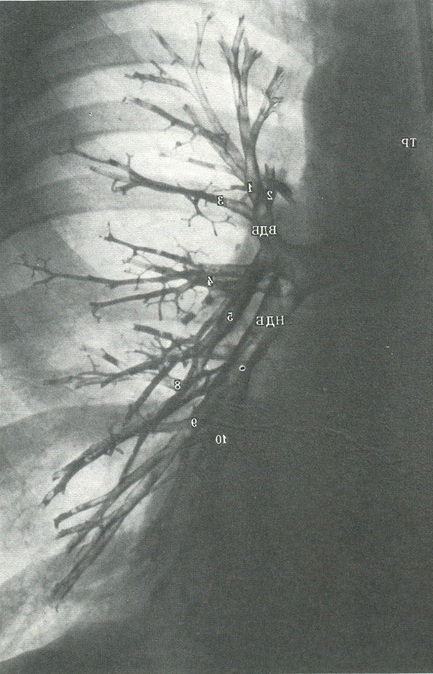

311. Нормальне бронхіальне дерево правої легені в прямій проекції (Б. К. Шарову).

TP - трахея; ГБ - головний бронх; ПРБ - проміжний бронх; ВДВ - верхнедолевой бронх; НДБ - нижньодольової бронх; 1 - верхівковий сегментарний бронх верхньої частки; 2 - задній сегментарний бронх верхньої частки; 3 - передній сегментарний бронх верхньої частки; 4 - латеральний сегментарний бронх (верхнеязычковый бронх для лівої легені); 5 - медіальний сегментарний бронх середньої частки (нижнеязычковый бронх для лівої легені); 6 - верхівковий сегментарний бронх нижньої частки; 7 - медіальний базальний сегментарний бронх нижньої частки; 8 - передній базальний бронх нижньої частки; 9 - латеральний базальний сегментарний бронх нижньої частки; 10 - задній базальний сегментарний бронх нижньої частки.